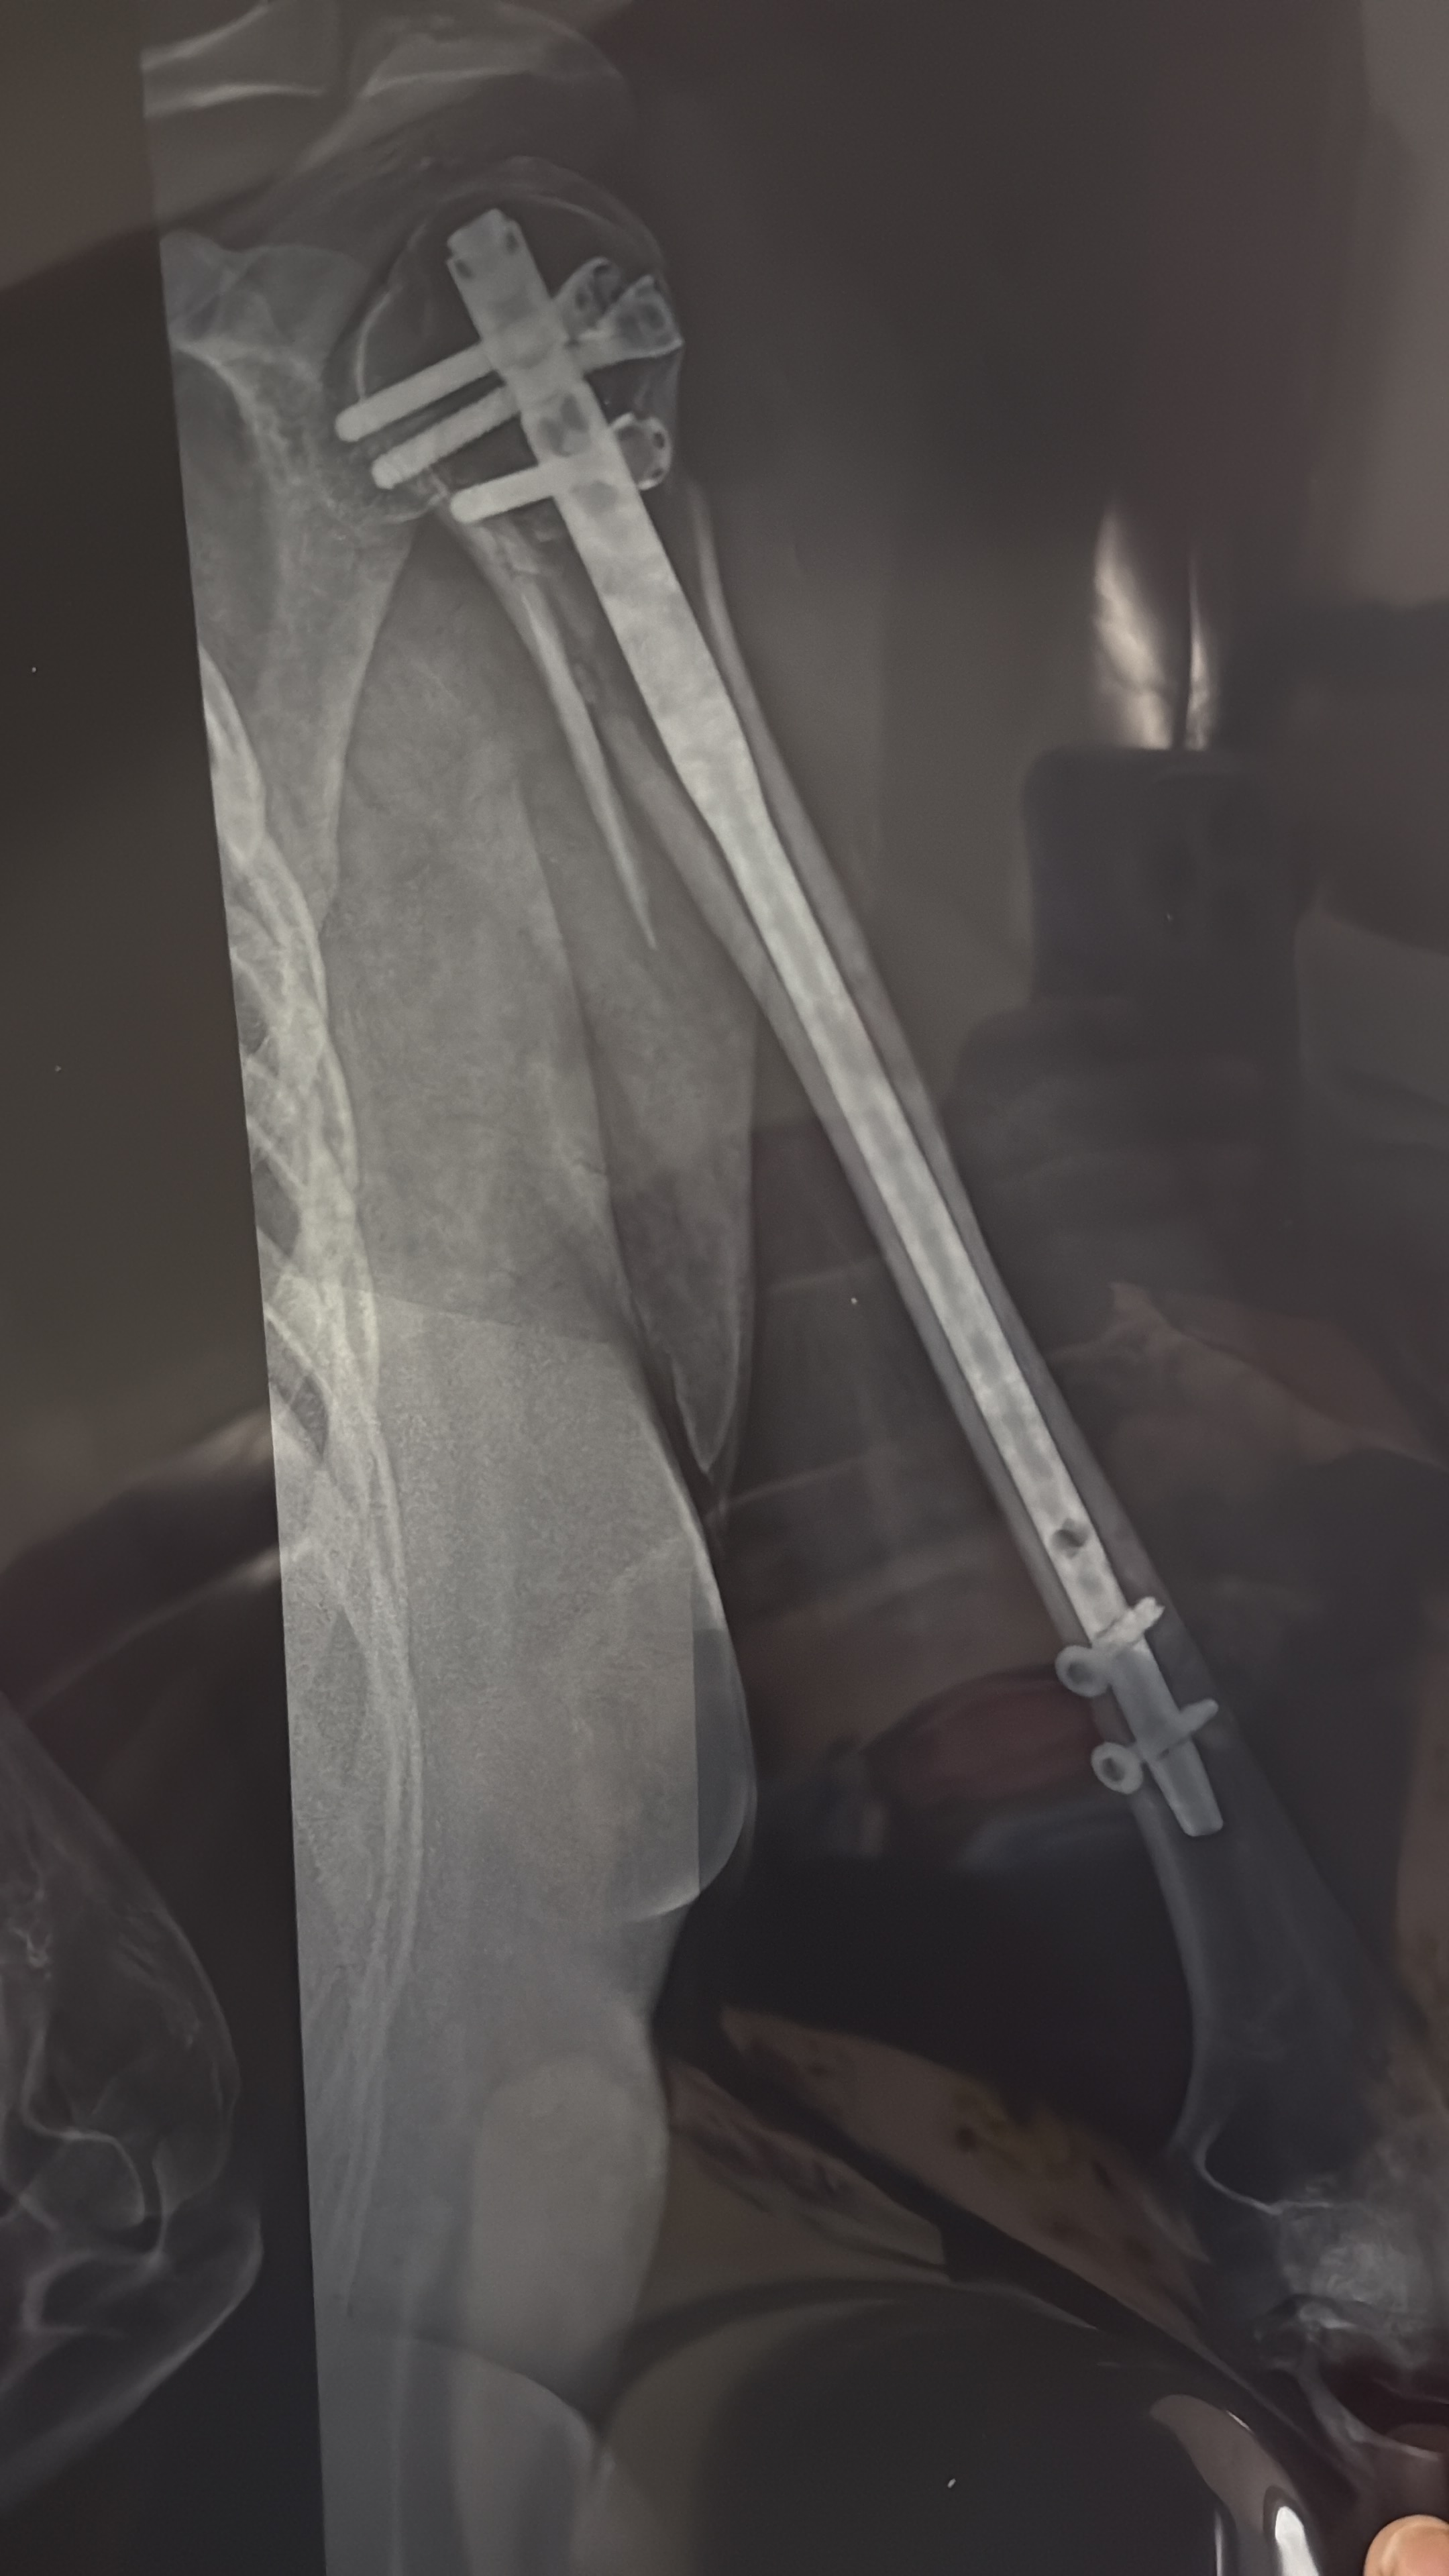

7 months ago I was involved in a serious car accident that resulted in a severe fracture. What followed was a whirlwind of pain and uncertainty. Because of the complexity of the injury, I had to undergo two major surgeries to stabilize my condition and begin the long process of healing.